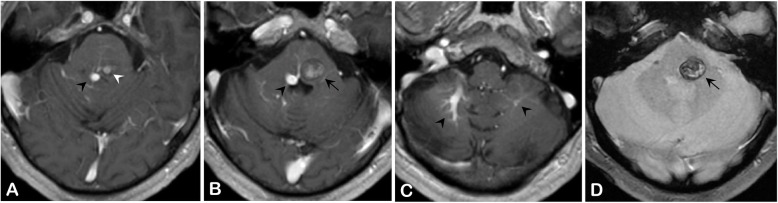

Fig. 2.

The cerebral MRI shows (a, white arrowhead, post-contrast T1-weighted sequence) a brainstem cavernous malformation (BCM) associated with (a,b,c, black arrowheads, post-contrast T1-weighted sequence) a bilateral cerebellar developmental venous anomaly (DVA) prevailing on the right side and draining into the vein of Galen. (b, black arrow, post-contrast T1-weighted sequence and D, back arrow, gradient-echo sequence) The BCM was responsible for a medial pontine hematoma